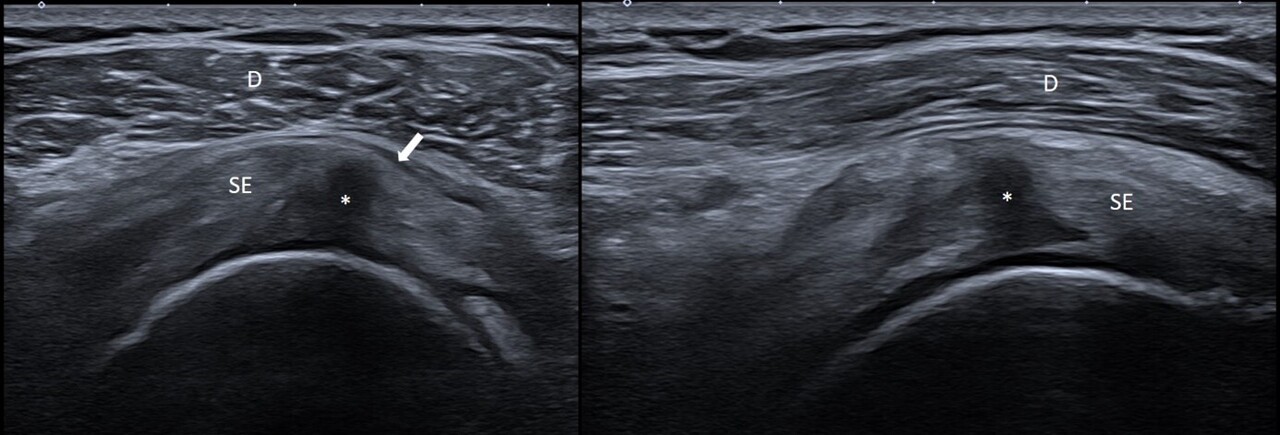

Tendinopathies et bursites

L’échographie permet d’identifier des signes de tendinopathie, des calcifications ou des ruptures partielles ou complètes des tendons, notamment au niveau de l’épaule (tendons de la coiffe des rotateurs) [fig. 1]. Elle permet également de détecter des bursites pouvant être la cible d’infiltrations sous échographie.

Cependant, il est important de noter la mauvaise corrélation radioclinique de ces anomalies, avec une fréquence importante de lésions asymptomatiques sur les examens échographiques, notamment de l’épaule. Dans une série de 51 patients asymptomatiques, des anomalies ont ainsi été mises en évidence chez 96 % des sujets ;2 les plus fréquentes étaient un épaississement de la bourse sous-acromiale sous-deltoïdienne, l’arthrose de l’articulation acromio-claviculaire et la tendinopathie du supra-épineux.

Ceci montre bien que les résultats échographiques doivent être interprétés en lien étroit avec les constatations cliniques afin que leur valeur diagnostique soit pertinente.